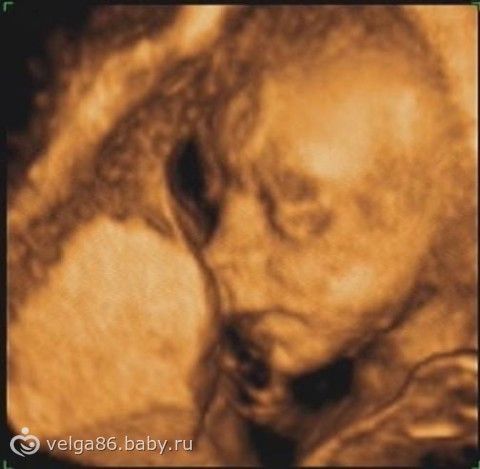

в общем срок у меня 19 недель и 2 дня, сегодня ездили на узи в клинику, которую нам посоветовала моя Г.

в общем когда мы зашли, она нам сразу сказала-сейчас ничего не спрашивайте, я буду работать, потом вам все расскажу, ладно, че-то там записывала, потом повернула миниэкранчик к нам, там ни хрена не видно, что она там увидела фиг знает, пол говорит не видно, срок слишком маленький (в 19 то недель), ну ладно, в итоге спросили про вес ребенка, сказала 620 грамм!!! я говорю чё-то многовато, она говорит, типа вторые детки обычно крупнее, ну ладно, а потом приехала домой и уже обдумала всё- по идее на таком сроке детки весят 250-350 грамм, ну никак не 650!!! все показания соответствуют сроку 19 нед. 4 дня, кроме головы, сказала, что головка немного больше… так вот еще чё думаю если она так с весом нам насчитала, остальное она правильно насмотрела?